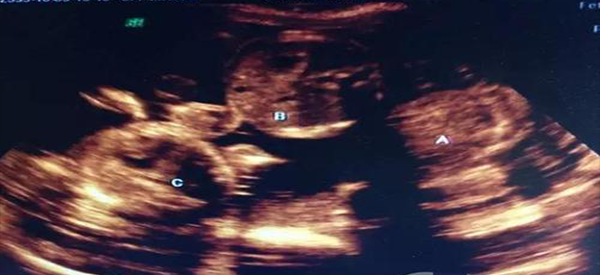

我和老婆由于自怀困难,所以到医院接受了试管婴儿治疗,昨天去医院检查发现坏了三胞胎,担心老婆的身体,所以我想了解一下试管三胞胎成活率高吗?

试管怀三胞胎属于多胎妊娠,也就是指一次妊娠宫腔内同时有两个或者两个以上的胎儿。一般来说,试管三胞胎势必会增加孕妇的身体负担,影响生命健康,同时也会影响胎儿的存活率和存活质量。

试管婴儿三胞胎成活率在15-20%

1、目前来说,试管婴儿多胎率为15-20%,试管三胞胎并发症以及死亡率都是极高的,所以一般存活率都是相当低的;

2、另外,由于多胎妊娠本身的风险就是比较大的,容易导致胎儿出现宫内死亡、生长发育迟缓以及畸形等情况,三个胎儿会互相争取营养和空间,因此存活的几率是相当小的。